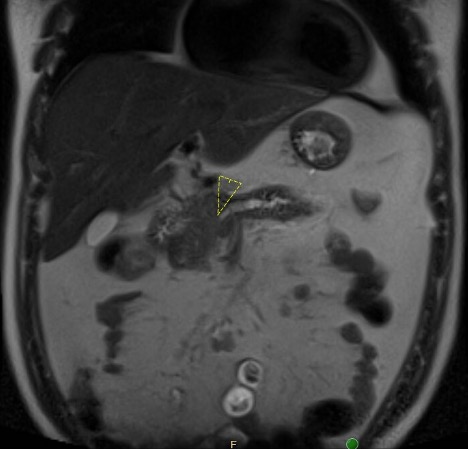

Case Presentation: A 29-year-old male with no medical history presented with abdominal pain and diarrhea after a trip to Key West. He described 2 days of constant epigastric pressure and cramping with no relation to food intake or bowel movements, along with 1 night of black, watery diarrhea. He denied fever, weight loss, night sweats, or easy bleeding/bruising. He endorsed daily binge drinking while traveling, with no consumption of raw shellfish, illicit drug use, or unprotected sexual encounters. He lived in rural North Carolina and owned dogs, chickens, and cats. He had a 5 pack year smoking history and used no medications. Family history was significant for a “lymph node cancer” in his father. At presentation, vital signs were T 37.1°C, HR 96 bpm, BP 185/100 mmHg, RR 18, and SpO2 96% on room air. Exam showed epigastric tenderness with no cervical lymphadenopathy or jaundice. Laboratory results showed WBC 11.7 x10*9/L (H), Hgb 12.7 g/dL, Platelets 371 x10*9/L, absolute neutrophil count 9.2 x10*9/L (H), and absolute lymphocyte count normal. Elevated studies included fibrinogen 585 mg/dL, lipase 1,100 U/L, CRP 30 mg/L, and ESR 30 mm/h. Notably normal studies included a complete metabolic panel, lactate, APTT, PT, INR, GI stool pathogen panel, C. difficile assay, and ova/parasite exam. Peripheral smear showed a mild normocytic anemia. CT abdomen/pelvis showed acute interstitial pancreatitis, dilation of the main pancreatic duct, and multistation adenopathy throughout the abdomen and pelvis. A magnetic resonance cholangiopancreatography (MRCP) showed multifocal abnormal soft tissue deposits within the pancreas obstructing the main pancreatic duct. Both studies suggested a concern for lymphoma. Malignant hematology was initially unimpressed with his case due to the near normal CBC and normal LDH and uric acid. As such, an infectious workup for diffuse lymphadenopathy was pursued and negative for HIV, syphilis, tuberculosis, tick-borne illnesses, bartonellosis, and toxoplasmosis. He underwent EUS/ERCP with main pancreatic duct stenting and biopsy. Pathology ultimately resulted as diffuse large B-cell lymphoma.